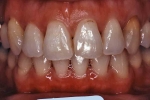

治療後5年経過時

治療前後の比較